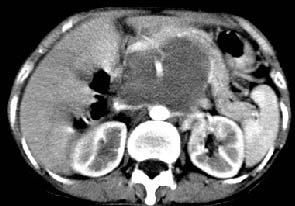

胰腺受压前移,胰管扩张,应为腹膜后占位,病灶密度不均,有低密度坏死区,强化扫描强化不明显腹腔干动脉受侵,考虑腹膜后恶性占位

从发病部位(腹主动脉周围)及增强方式(均匀轻度强化、少量坏死)和病变形态(较大、多结节形)符合腹膜后淋巴瘤,建议颈部病变活检。

我的第1诊断还是考虑是淋巴类病变1}。从病灶形态上看不是很规则,但其更向是多个结节的融和,其内有少许坏死,整个病灶的强化不是很明显,临近左恻肠间隔有增厚,2}我认为更重要的一点的是肠系膜有明显增厚呈片状。3}患者的脾脏不大其未见异常病灶。结合以上几点我首先考虑是转移性{但对此诊断我觉得不足之处;转移性的淋巴结肿大融合为什么没有坏死?}。{另外患者无大便习惯改变及血便,其发现右颈包块在今年过年无意发现}。以上是我的浅分析望各位战友继续讨论!谢谢!!

主动脉-胰腺间隙可见巨大分叶状软组织肿块影,包绕腹主动脉、腹腔干及其分支、腔静脉等大血管,增强呈无明显强化,临近脏器明显受压移位,增强示有分界。肝右叶可见局限性低密影,边缘清楚。

讨论:首先看肠系膜和腹膜后的肿块我认为是多发融合的肿大的淋巴结。理由1大小不等的分叶,分布比较

自由。2其中的包绕的血管和周围少量的脂肪即所说的。

同时胃的影象表现和临床的不典型表现,所以我认为淋巴瘤,临床表现不支持胃癌